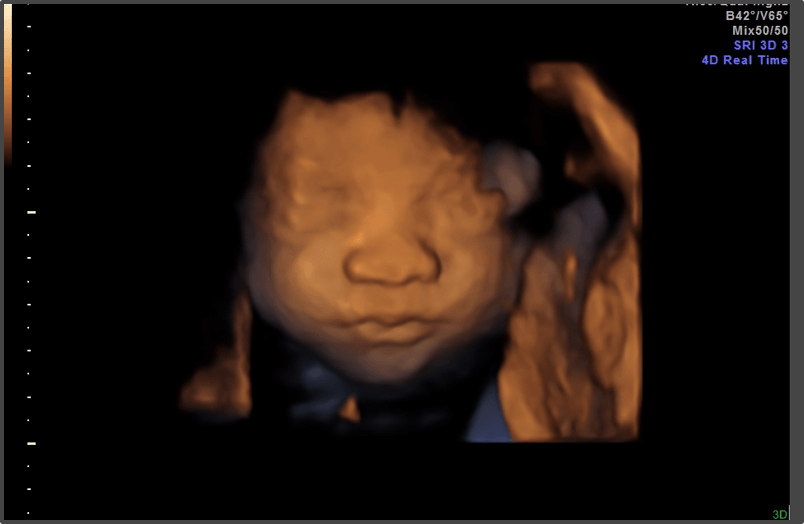

Your baby is the size of a head of cauliflower.

Baby is the size of Cauliflower

Approx Baby Weight: 870g

Approx Baby Size: 36.6 cm

Baby Development

The baby’s lungs are developing the ability to breathe.